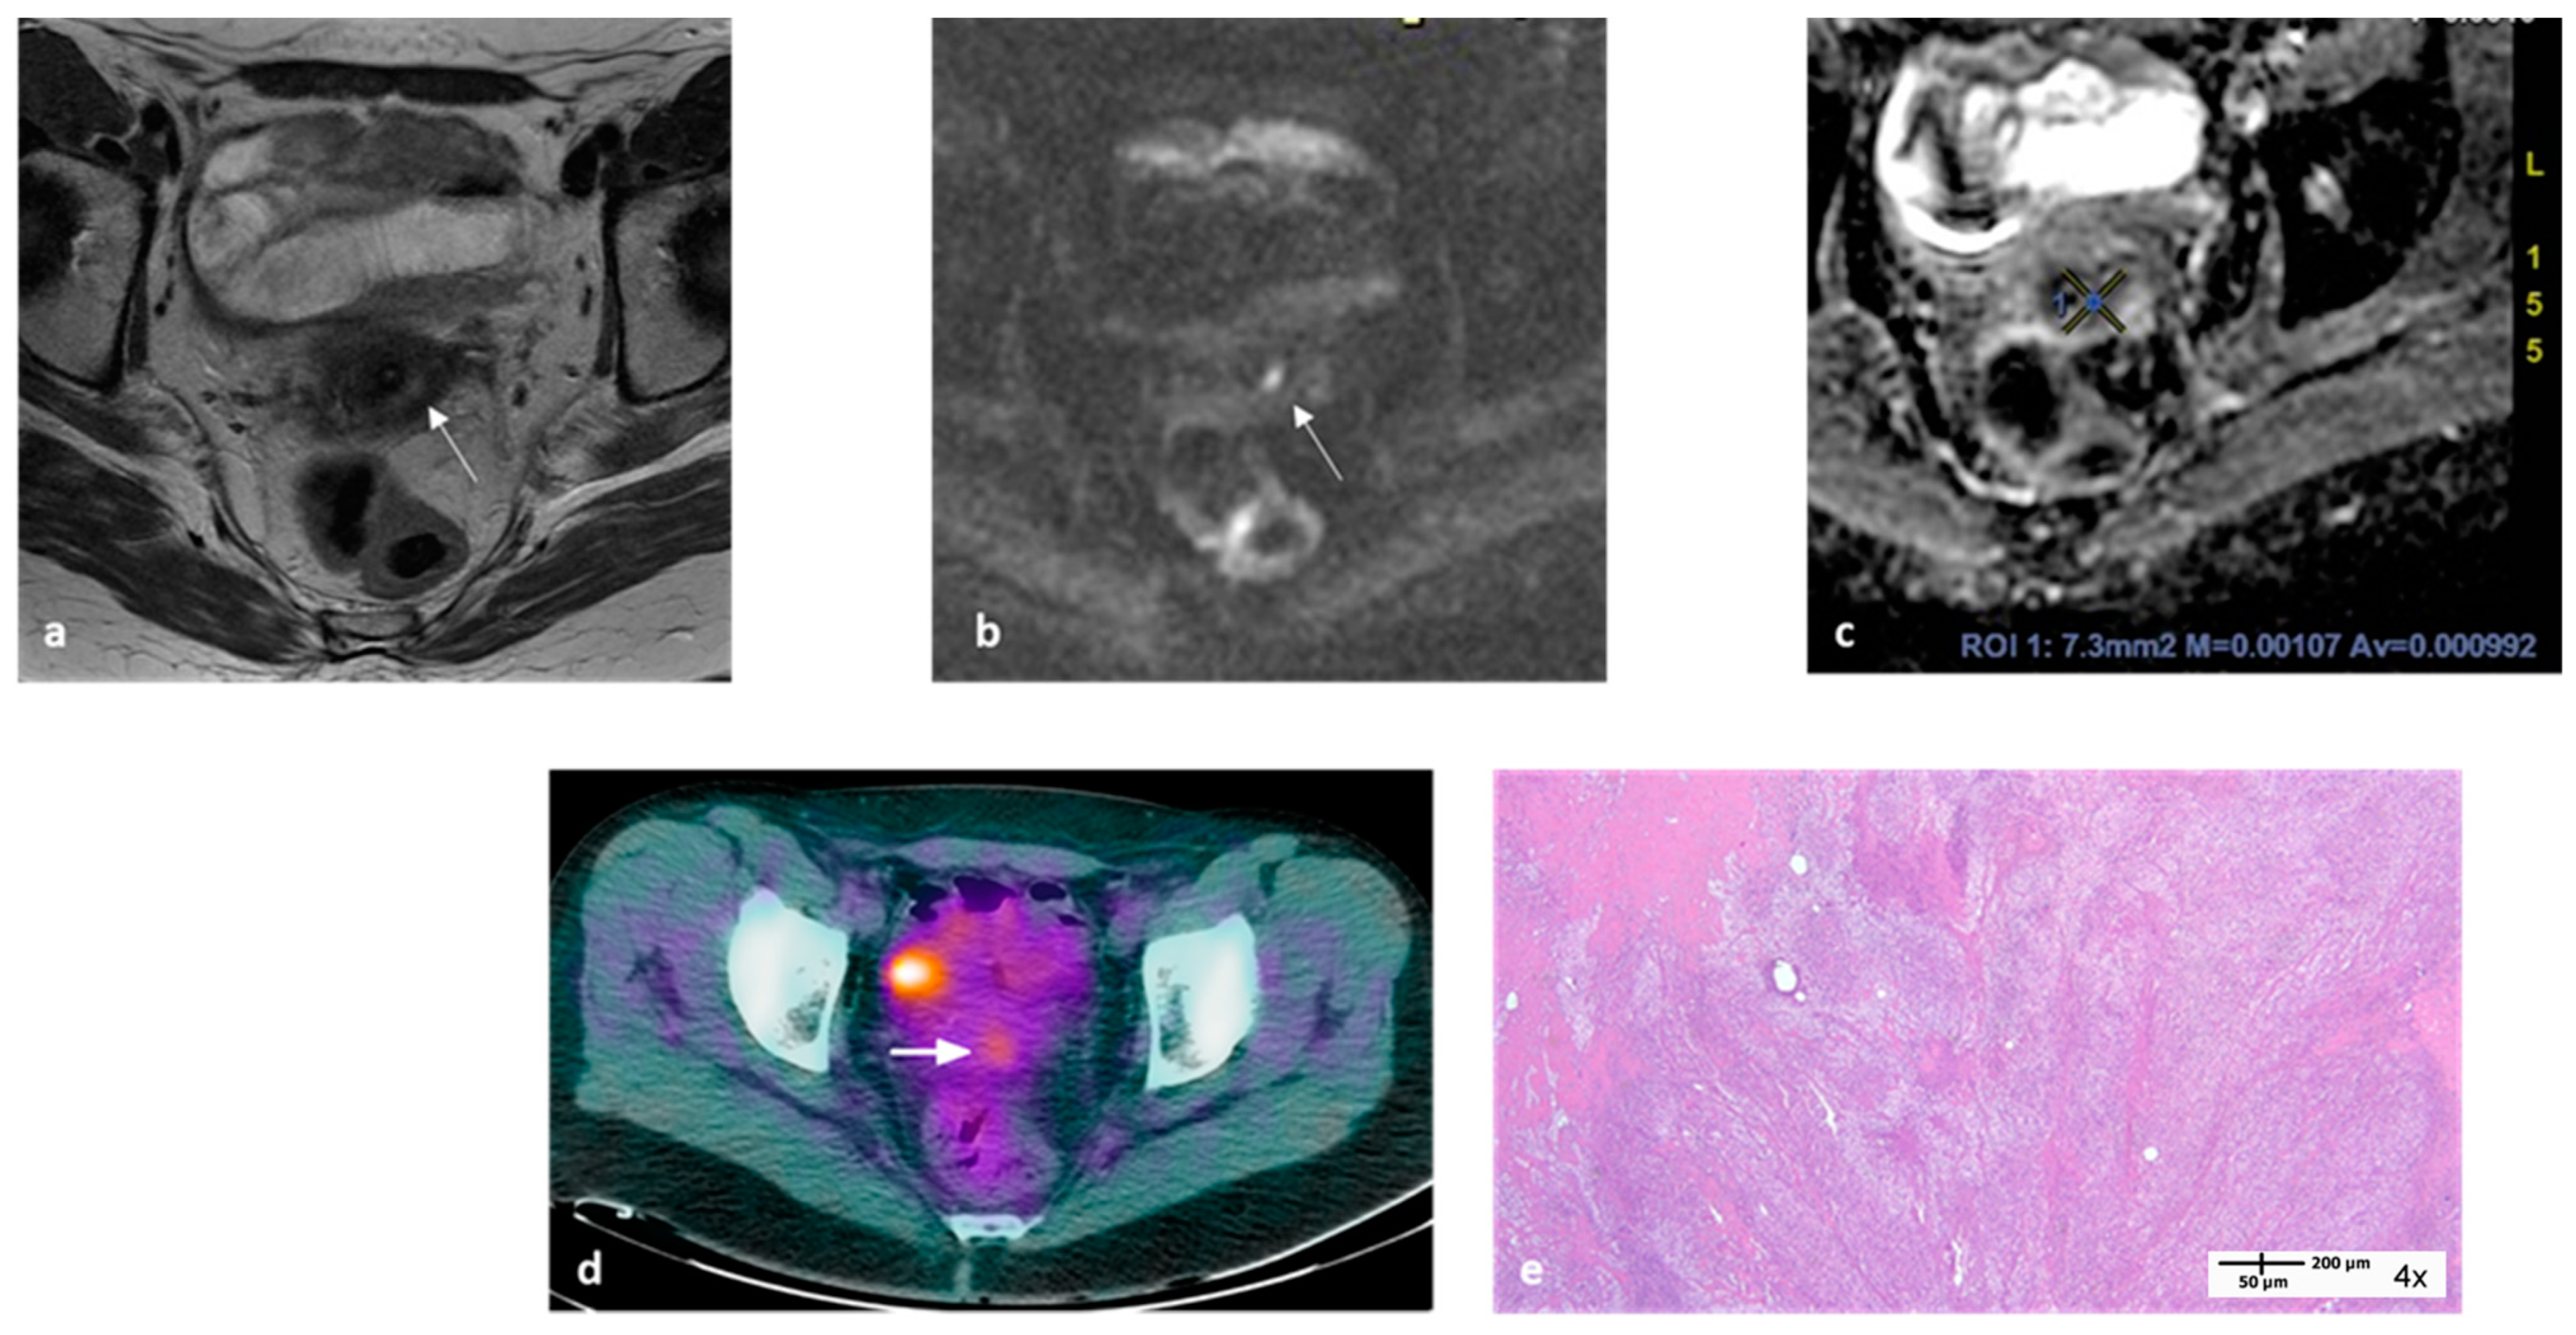

- Valentini, A.L.; Miccò, M.; Gui, B.; Giuliani, M.; Rodolfino, E.; Telesca, A.M.; Pasciuto, T.; Testa, A.; Gambacorta, M.A.; Zannoni, G.; et al. The PRICE study: The role of conventional and diffusion-weighted magnetic resonance imaging in assessment of locally advanced cervical cancer patients administered by chemoradiation followed by radical surgery. Eur. Radiol. 2018, 28, 2425–2435. [Google Scholar] [CrossRef] [PubMed]

- Gui, B.; Miccò, M.; Valentini, A.L.; Cambi, F.; Pasciuto, T.; Testa, A.; Autorino, R.; Zannoni, G.F.; Rufini, V.; Gambacorta, M.A.; et al. Prospective multimodal imaging assessment of locally advanced cervical cancer patients administered by chemoradiation followed by radical surgery-the “PRICE” study 2: Role of conventional and DW-MRI. Eur. Radiol. 2019, 29, 2045–2057. [Google Scholar] [CrossRef] [PubMed]

- Rufini, V.; Collarino, A.; Calcagni, M.L.; Meduri, G.M.; Fuoco, V.; Pasciuto, T.; Testa, A.C.; Ferrandina, G.; Gambacorta, M.A.; Campitelli, M.; et al. The role of (18)F-FDG-PET/CT in predicting the histopathological response in locally advanced cervical carcinoma treated by chemo-radiotherapy followed by radical surgery: A prospective study. Eur. J. Nucl. Med. Mol. Imaging 2020, 47, 1228–1238. [Google Scholar] [CrossRef] [PubMed]